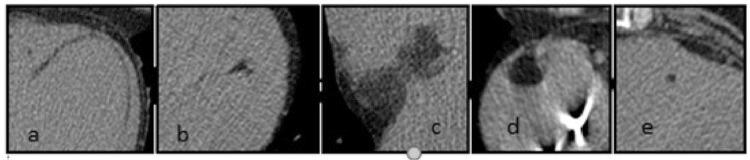

204 subjects (11.1%) had FR within the heart (113 men; 91 women; mean age 57.8 years); 66% of fatty foci were seen only in the native scanning. The distribution of the fat was: right ventricle (RV) 31.9%, left ventricle (LV) 21.5%, biventricular 39.7%, interventricular or atrial septum 5.9%, and atria 1%. In the RV, fat was localized mainly in the papillary muscles, while in the LV fat was mainly subendocardial (p<0.001). The morphology of the fat was: linear 61.6%, oval 14.8%, punctuate 10.6%, irregular 10.2%, and bilobular 2.8%. Fat was primarily located subendocardially in the LV in patients after myocardial infarction. In patients with suspected coronary artery disease, it was mainly observed subpericardially in the RV and in papillary muscles (p<0.001).

204例受试者(11.1%)心脏内存在FR(男性113例;女性91例;平均年龄57.8岁);66%的脂肪灶仅在平扫时可见。脂肪分布情况为:右心室(RV)31.9%,左心室(LV)21.5%,双心室39.7%,室间隔或房间隔5.9%,心房1%。在右心室,脂肪主要位于乳头肌,而在左心室,脂肪主要位于心内膜下(p<0.001)。脂肪形态为:线状61.6%,椭圆形14.8%,点状10.6%,不规则形10.2%,双叶形2.8%。心肌梗死后患者的脂肪主要位于左心室心内膜下。在疑似冠心病患者中,主要在右心室的心包下和乳头肌中观察到脂肪(p<0.001)。